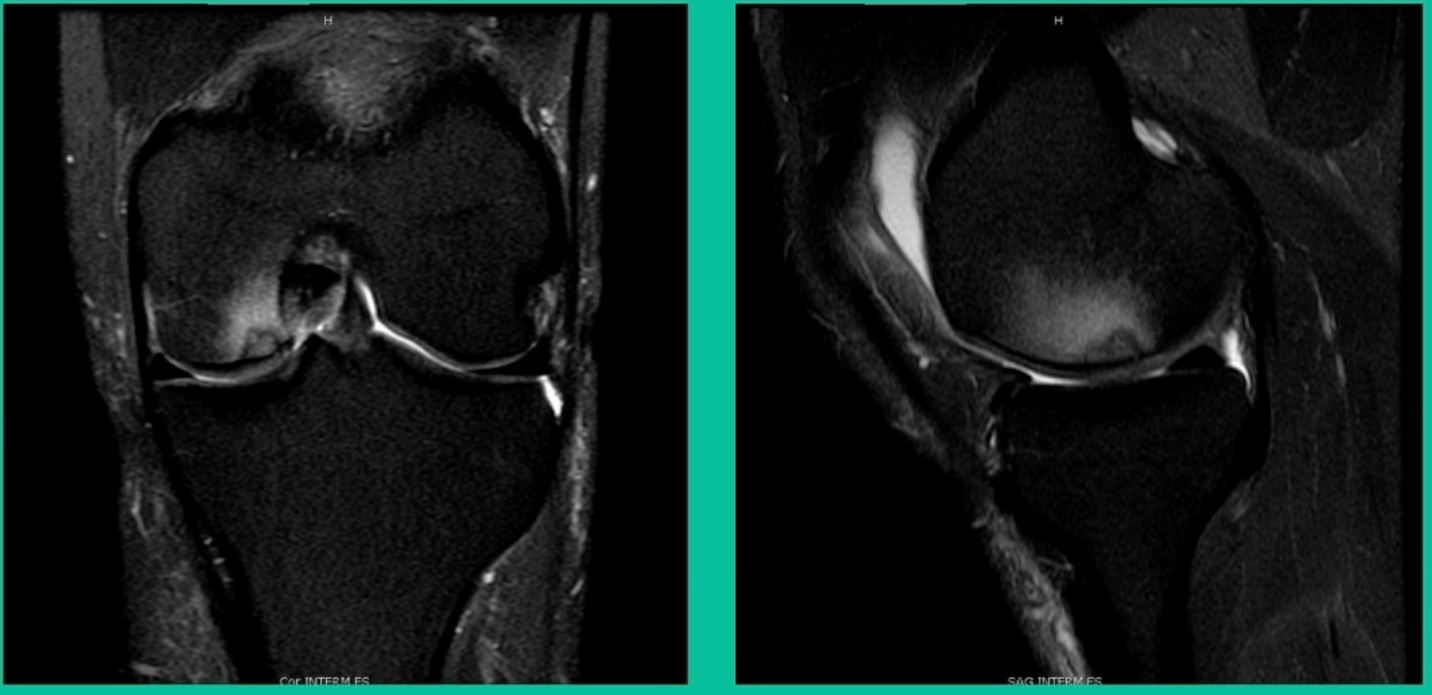

This is an 18-year-old with a lateral femoral condyle OCD:

Worsening over the last two years, has effusions but no locking, and has a large area of involvement that appears unstable. This is the classic fixation. If you can do this, this is the holy grail. Remember, fracture non-union: you elevate it, debride the base, get rid of any unstable fragments, just take them out, and preserve the major fragment. I’ll use a microfracture awl, but most commonly now I’ll use a pick or a pin, and I’ll drill it. I use two to three metal screws. I bury their heads, and then I come back at eight weeks after being non-weight-bearing, and pull the screws out.

Afterwards, I’ll allow them to fully weight-bear, wait eight more weeks, and then they go back to full sports. How do these do? Amazing. If you can get this to heal in an adult, this should last hopefully forever. The results over here show 80 to 90 percent healing rates in most series.